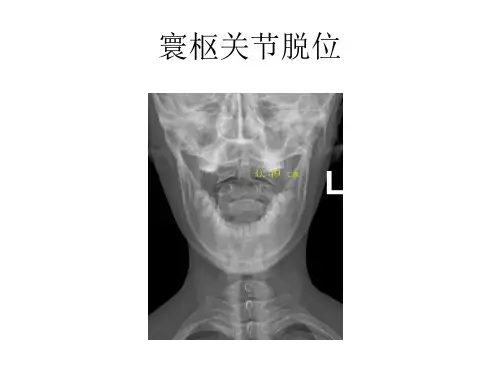

寰枢关节脱位